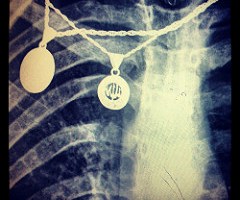

Blog, Paciente ¿Qué ropa y complementos son adecuados para el Paciente en sus pruebas de radiología? 11 de febrero de 2016 — 8 comentarios